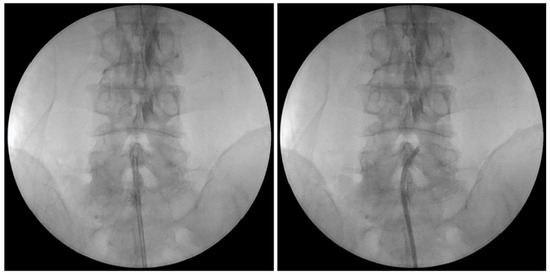

2.5. PEN with Steering Catheter